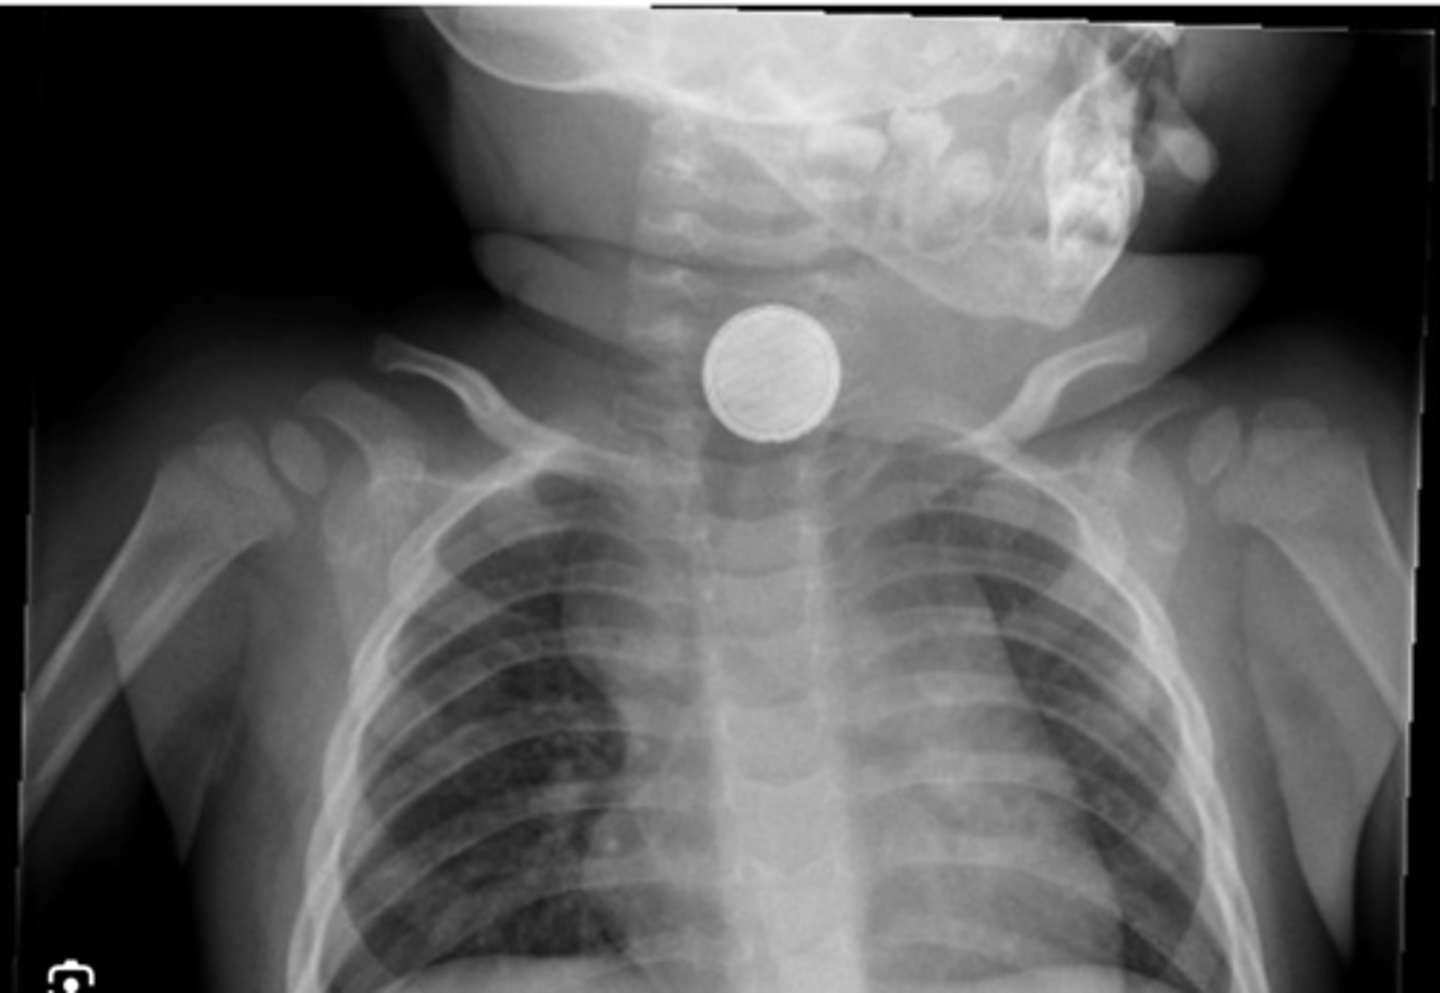

- Coins & Batteries

Why are button batteries dangerous when ingested?

- when ingested, button batteries react with water & cause alkaline caustic injury i.e. tissue liquefaction within 2 hours.

- it could lead to damage to oesophageal tissue, intestinal tissue, arterial etc. Could even lead to death.